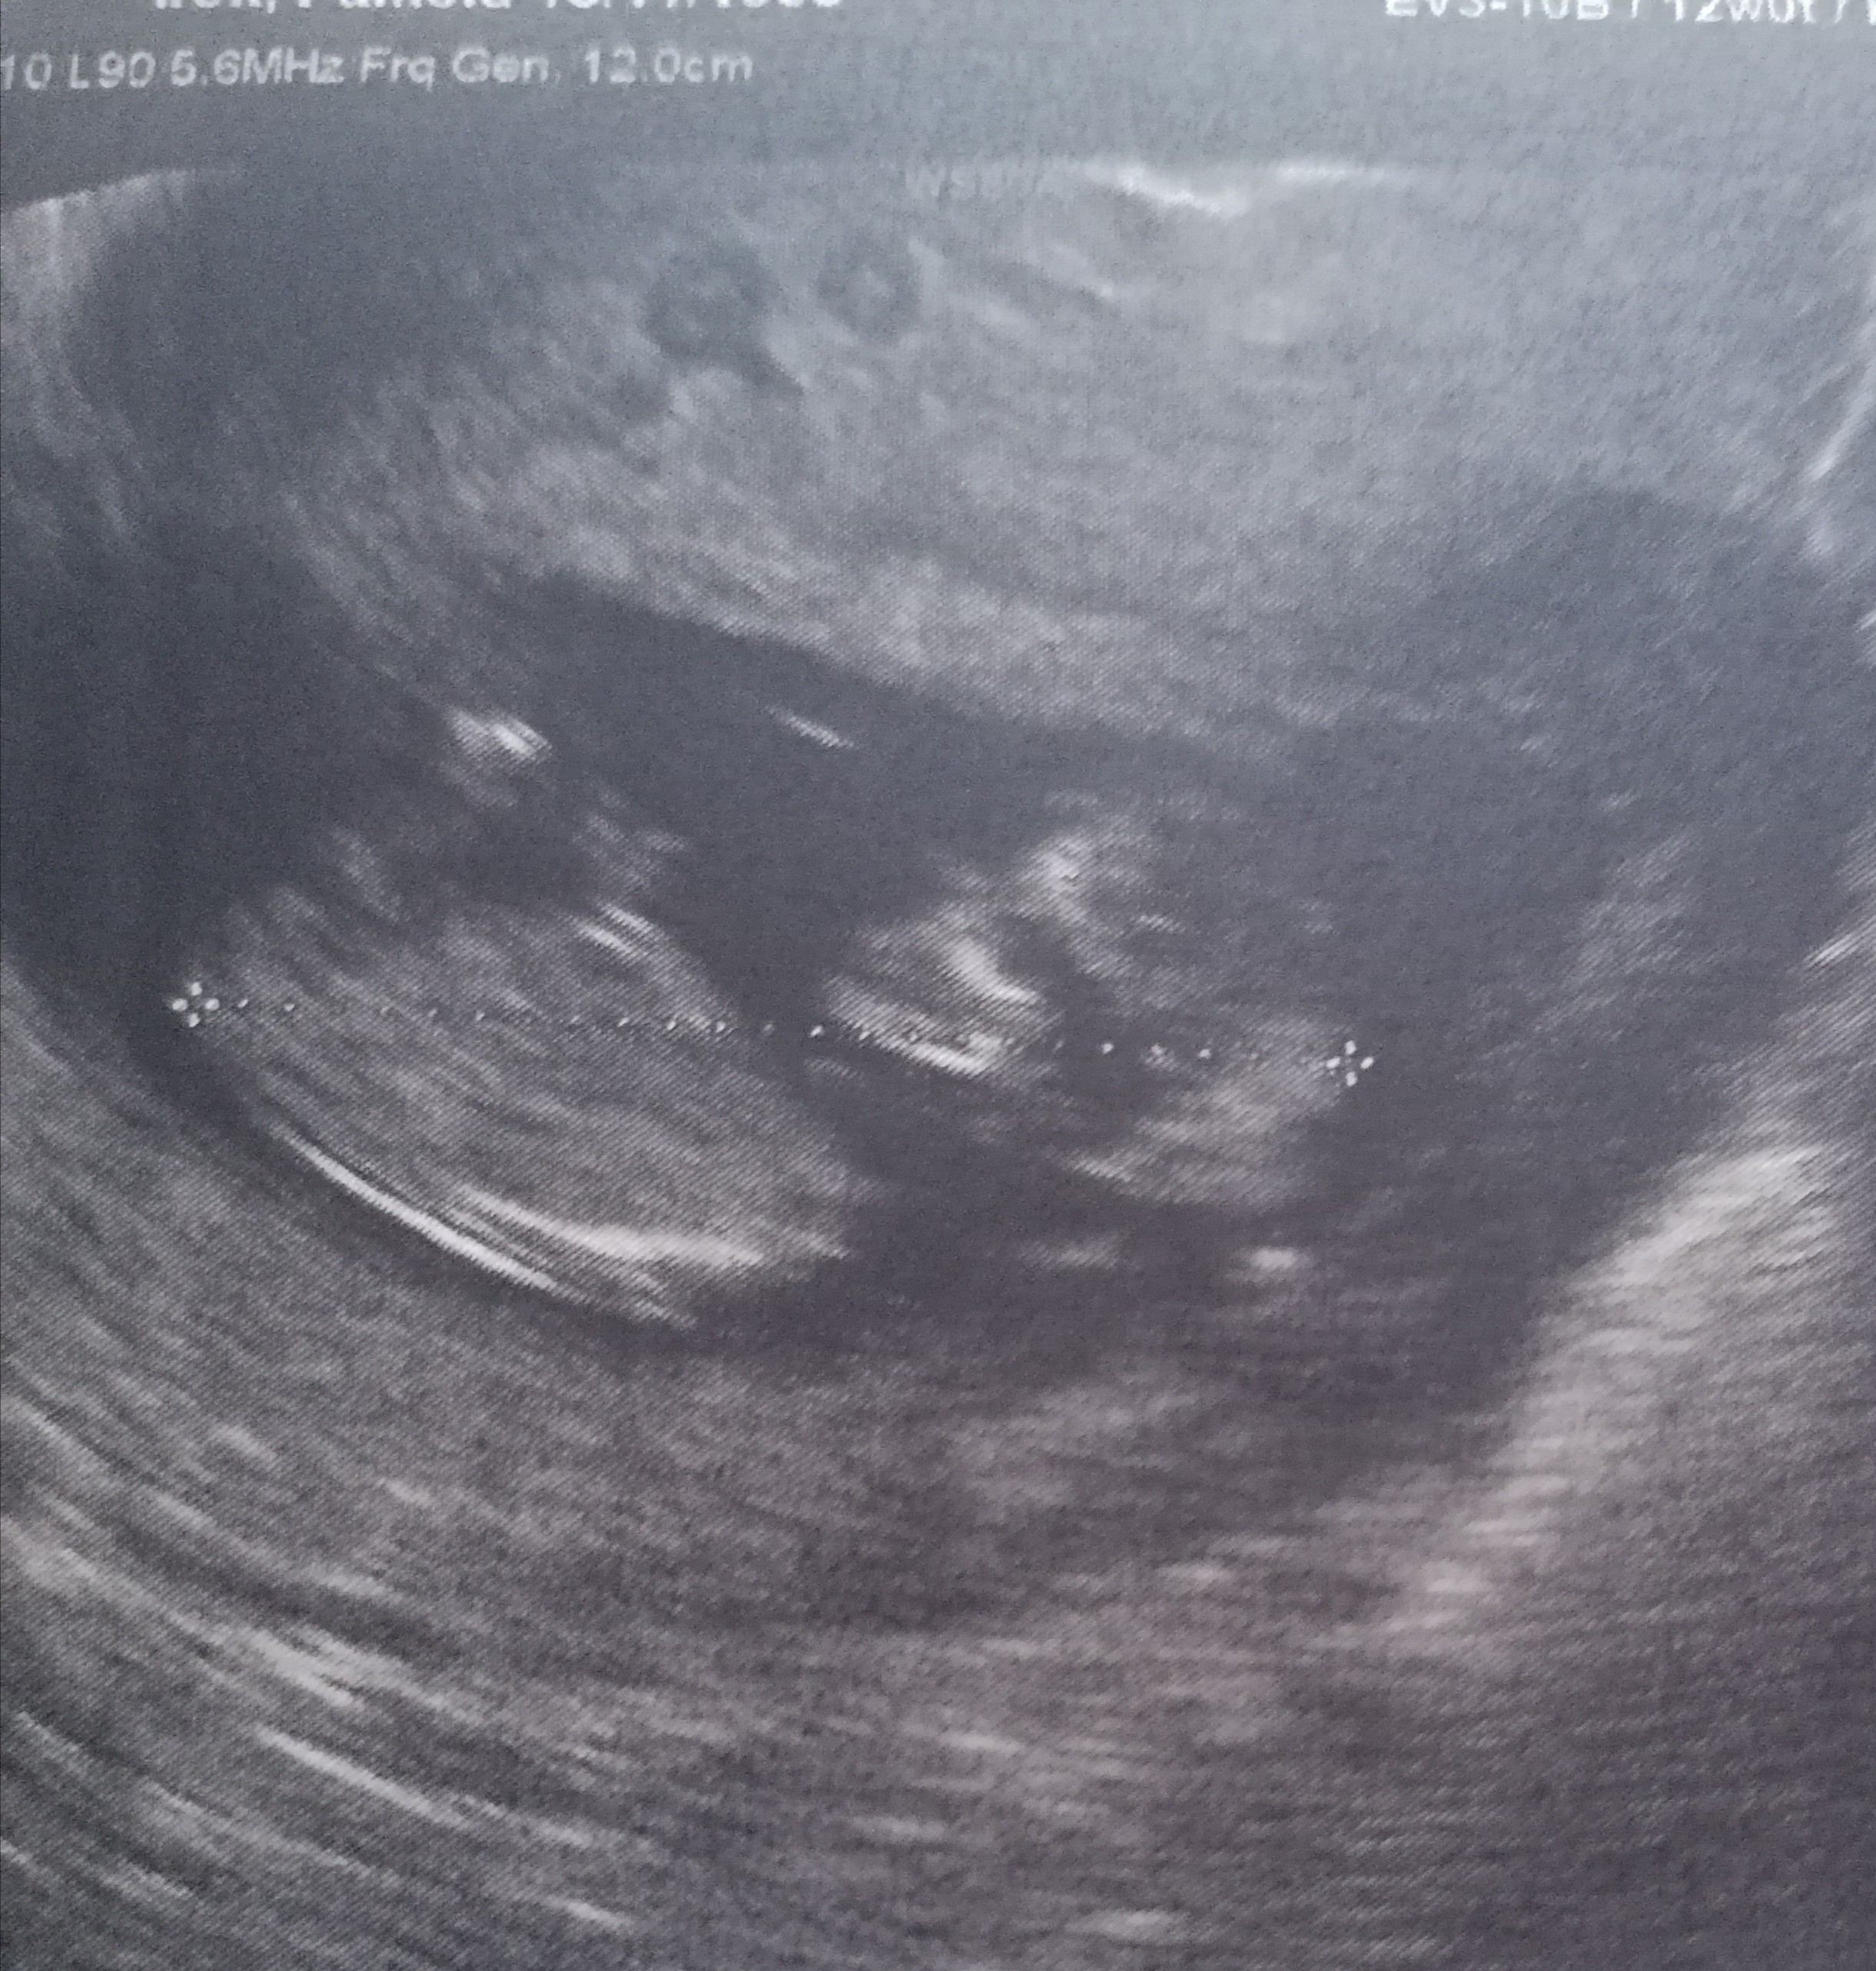

Dzień dobry!! Miałam się meldować co jakiś czas podczytuje nadal was i dziś pisze 😘 do wszystkich które mają chwilę zwątpienia i dołki nie poddawać się i u was sie uda ❤️ jak większość wie u mnie 4 transfery 2 stymulacje 1 biochemiczna a teraz 15tc bez mdłości i problemów jedyne co mi wcześniej dokuczało to ból głowy maluszki odwdzięczają się mamie za walkę! Ciekawe czy tak będę mówić jak zaczną kopać 🤣👍 są zdrowe mają się dobrze termin porodu na 3.09 ale lekarze mówią że do polowy sierpnia będą już z nami ❤️ trochę się chwilami boję ale już je kochamy ponad wszystko..powtarzam walczyć i nie poddawać się! Chociaż czasem jest mega trudno i nie ma się sił jest warto ❤️ życzę wam wszystkim pozytywnych bet i upragnionych dwoch kresek ❤️i pięknej spokojnej ciazy❤️ przesyłam nasze bąbelki pewnie są już większe ale zdjęcie mam sprzed 3 tyg ❤️

• IMG_20200220_134542.jpg

IMG_20200220_134542.jpg

1,1 MB · Wyświetleń: 97